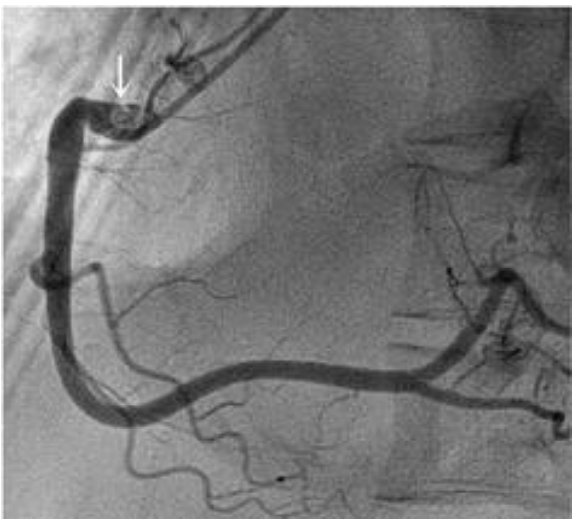

Mulher de 68 anos, com hipertensão e dislipidemia, foi atendida na emergência devido à dor torácica com 90 minutos de evolução. O

eletrocardiograma de admissão foi compatível com uma síndrome coronariana aguda com supradesnível de ST de parede inferior.

Encaminhada imediatamente à hemodinâmica e submetida à angioplastia com implante de stent no segmento proximal da coronária

direita com sucesso. Houve resolução da dor e do supradesnível do segmento ST, e não havia lesões residuais. Mantida dupla antiagregação

plaquetária, ao ser internada na unidade cardiointensiva seu eletrocardiograma revelou o traçado abaixo. No momento do registro a

paciente estava assintomática, com frequência cardíaca 70 bpm, pressão arterial 124x66 mmHg, e sem sinais de congestão pulmonar.